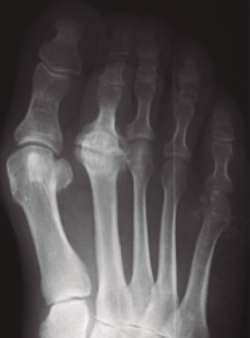

Figura 6. Tratamiento quirúrgico. La resección aislada de la cabeza suele dar malos resultados.

- Resección de la cabeza del metatarsiano. Esta técnica clásica propuesta por algunos autores(18,19,20) elimina el dolor articular pero tiene el grave inconveniente de que provoca una importante desalineación del antepié con la correspondiente metatarsalgia de transferencia (Figura 6).

Figura 9. Esquema de la queilectomía. Resección de la corona osteofítica del metatarsiano y de la falange. Extirpación de cuerpos libres. Se asocian perforaciones anterógradas o retrógradas.

Figura 10. Queilectomía. Resultados a largo plazo. A: preoperación; B: postoperatorio inmediato; C: 17 años postoperación.